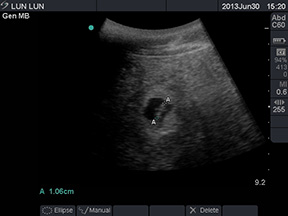

超声波检查

今年3月,“伦伦”进入了发情高潮期,美国史密桑林保护生物所的大熊猫繁殖生理学专家Copper Aitken-Palmer博士为“伦伦”做了人工授精。6月30日,美国亚特兰大动物园专家通过超声波检查了“伦伦”腹中胎儿的大小,长度为1.08厘米。兽医部和动物管理部专家根据“伦伦”2010年生第三胎“阿宝”时的类似超声波检查数据推测,这只小宝宝估计将于两周至三周后出生。